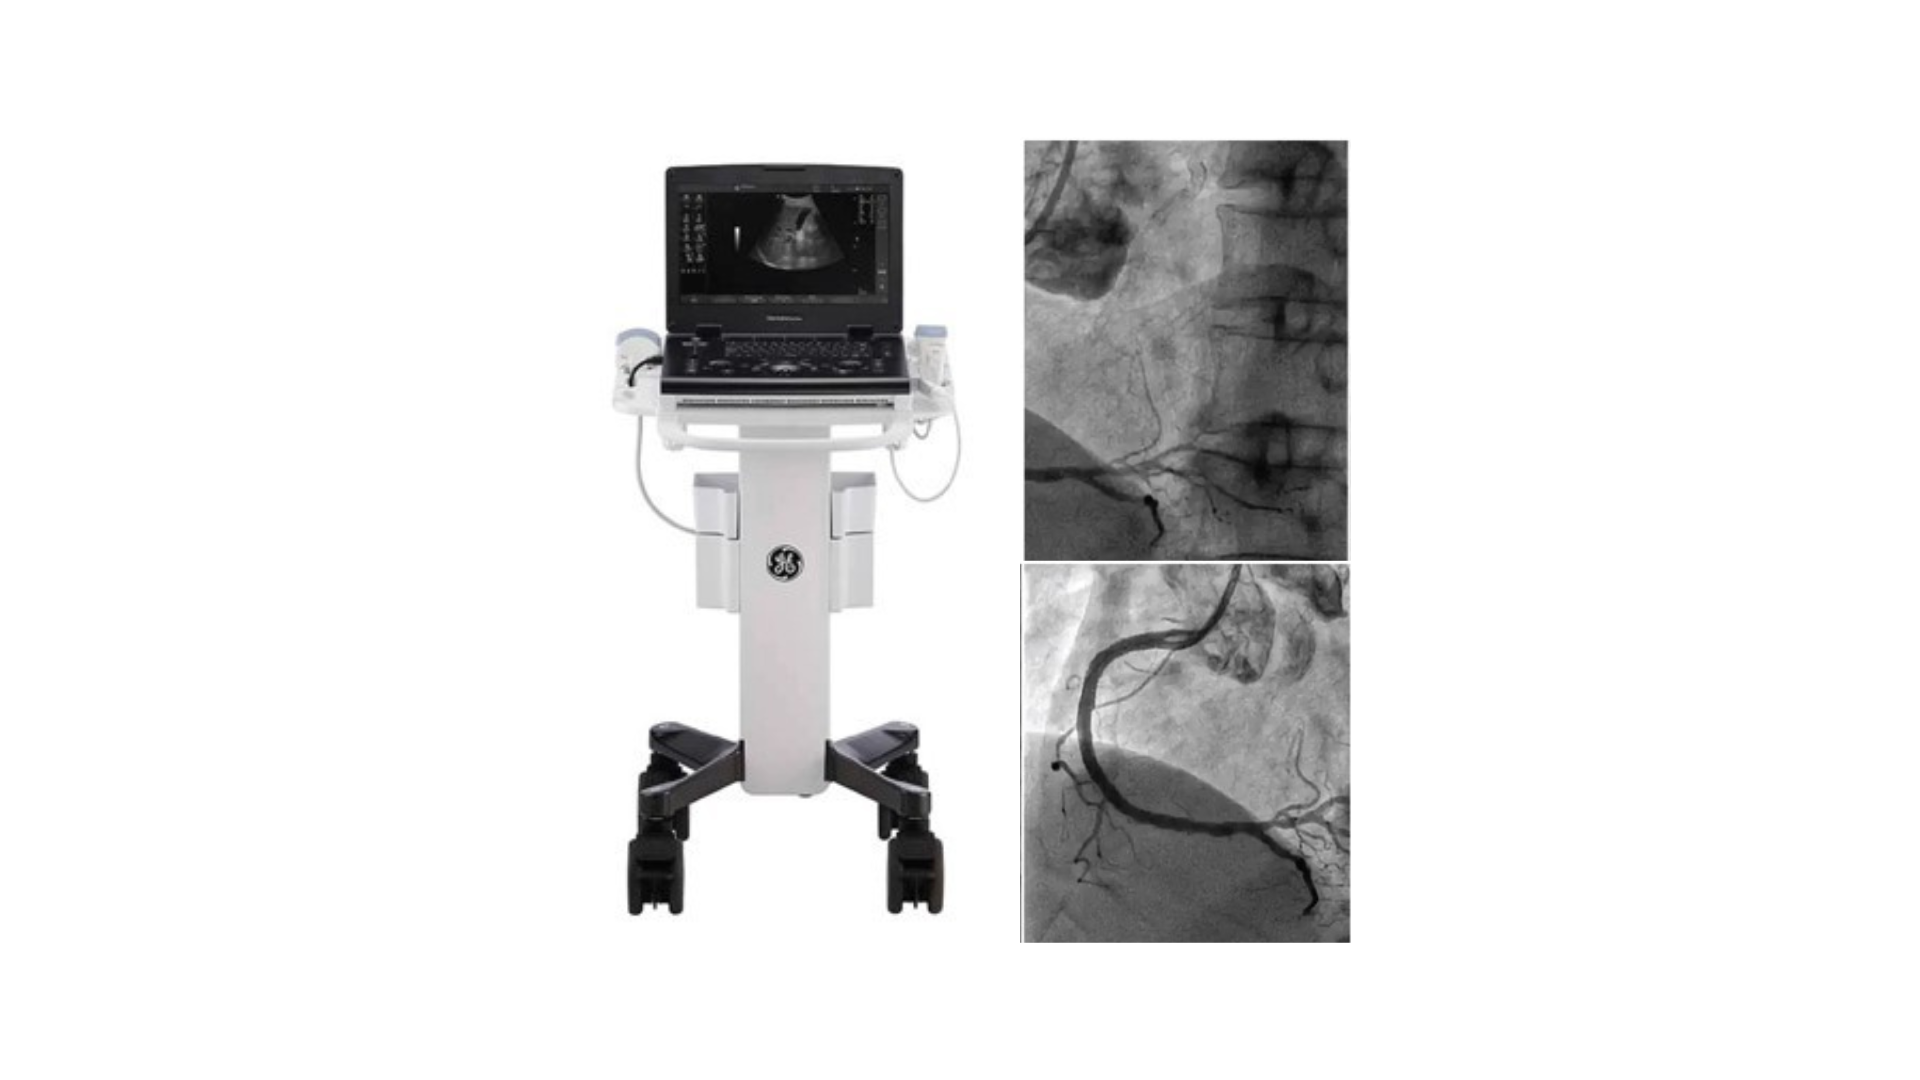

How EECP is Performed

Enhanced External Counter pulsation (EECP) is a non-invasive therapy performed with the patient lying comfortably on a treatment table. Large inflatable cuffs are wrapped around the calves, thighs and hips. These cuffs inflate sequentially during the relaxation phase of the heartbeat (diastole), pushing blood back toward the heart and improving coronary perfusion. They then deflate just before the heart contracts (systole), reducing the resistance the heart must pump against. Each session typically lasts about 1 hour and a full treatment course usually consists of 30–35 sessions over 6–7 weeks.